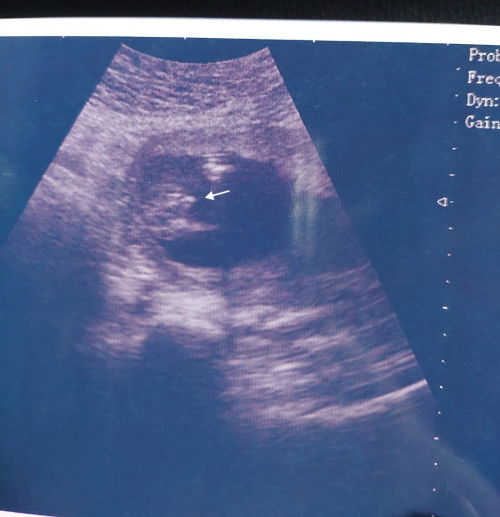

Hello moms , pinjam mata kejap ... Ni gender boy or girl ? Dr. kata boy . Sya scan 15w5d kat klinik swasta. Percentage utk silap tu ada tp dah cuba check 3x Dr. nampak gender yg sama. Ada tak moms kat sini pgalaman ada baby boy scan gender mcm dkt gambar ni ? Sya tak ada pglaman lg sbb sblm ni klr 2 girls harap kali ini boy betul la. #inginkepastian